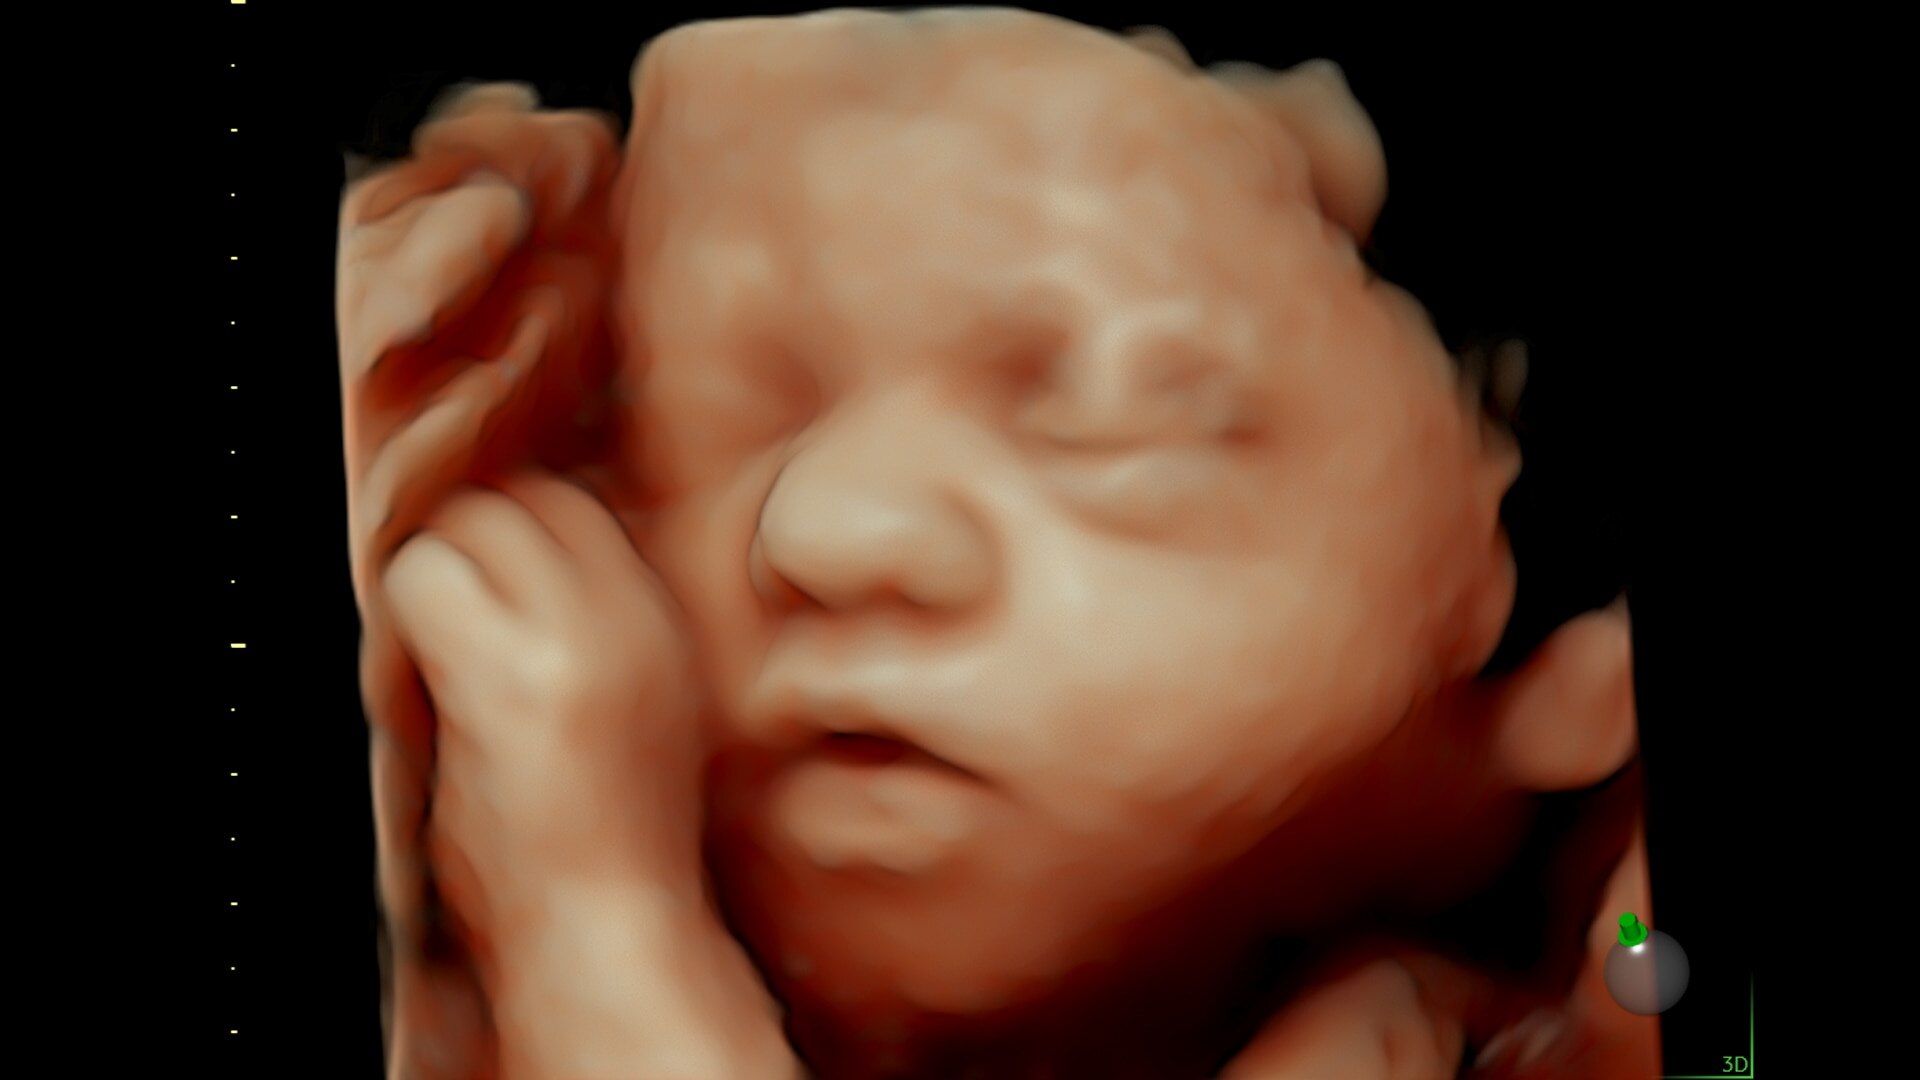

Get great images fast.

Advanced beamforming capabilities work in harmony with expert-level probes to deliver faster processing speeds and frame rates for enhanced detail and contrast resolution, greater color quality and sensitivity, and exceptional 3D/4D.